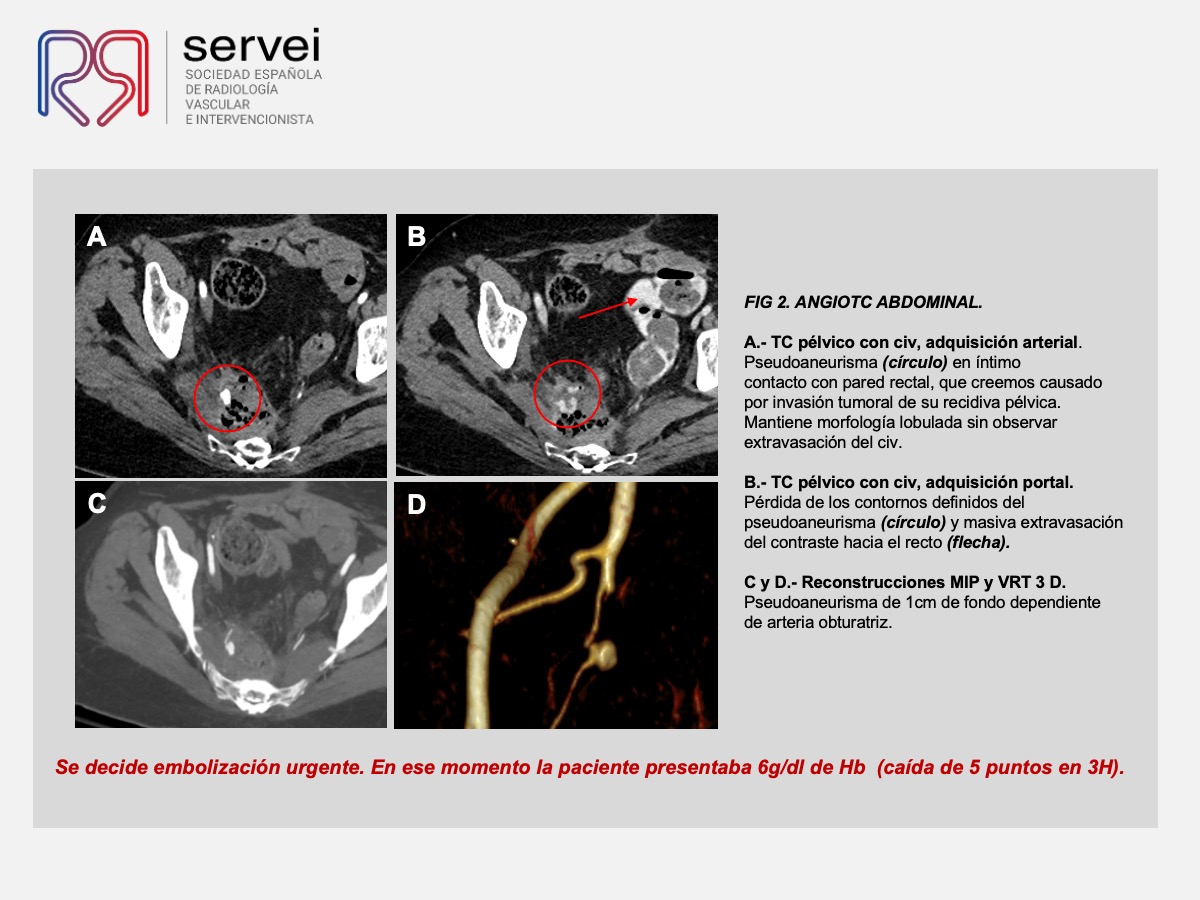

- Pseudoaneurisma arteria obturatriz-rectorragia 01

- Pseudoaneurisma arteria obturatriz-rectorragia 02

- Pseudoaneurisma arteria obturatriz-rectorragia 03

- Pseudoaneurisma arteria obturatriz-rectorragia 04

- Pseudoaneurisma arteria obturatriz-rectorragia 05

- Pseudoaneurisma arteria obturatriz-rectorragia 06

- Pseudoaneurisma arteria obturatriz-rectorragia 07

- Pseudoaneurisma arteria obturatriz-rectorragia 08

- Pseudoaneurisma arteria obturatriz-rectorragia 09